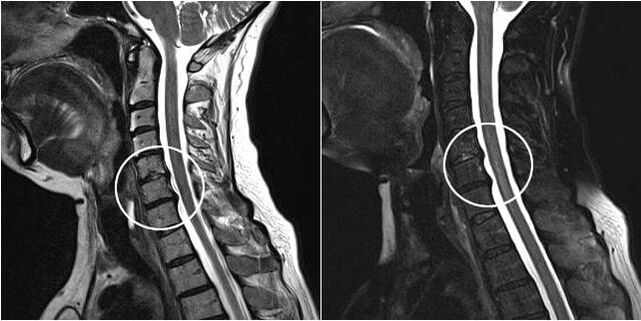

Surgical intervention

Indications for surgical intervention, inefficiency of conservative treatment, as well as complications of cervical osteochondrosis, for example, myelopathy, vertebral artery syndrome and radicular syndrome.To decompress the spinal cord, blood vessels and spinal roots, the following operations:

During surgery, bone fragments and ligaments can be resected, and intervertebral discs can be removed in whole or in part.For small herniated disc protrusions, laser ablation of the disc nucleus is often performed.

After extensibility of the lamellar structures, stabilization of the spinal motion segments is often required, with spinal fusion or placement of bone and dermal autografts.